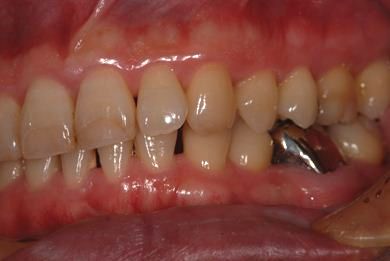

| 性別/年齢 | 男性 / 37歳 | ||||||||||||||||||||||||||||||||

| 主訴 | 前歯(2本)の欠けの治療 | ||||||||||||||||||||||||||||||||

| 治療方針 | 右下欠損部分をインプラント治療にて、機能的・審美的回復を行う。 | ||||||||||||||||||||||||||||||||

| 治療内容 | インプラント1本、メタルボンドセラミッククラウン1本 | ||||||||||||||||||||||||||||||||